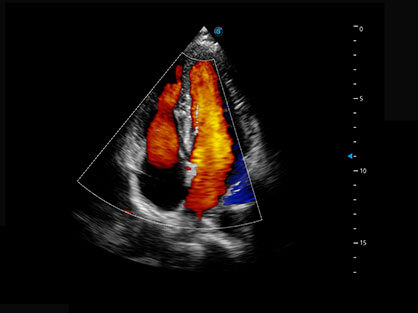

通过对组织运动信息、血流信号及背景噪声进行准确智能的阈值判定,高效提取出微弱血流信号,获得高灵敏度和空间分辨率的血流图像,为临床提供更加真实和丰富的诊断信息。